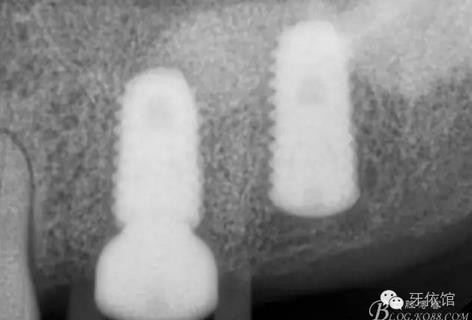

X光片

術后x光片,右上6直接上愈合基臺,但未完全就位,右下7手術過程略

這是術后1月的片子,重新就位愈合基臺